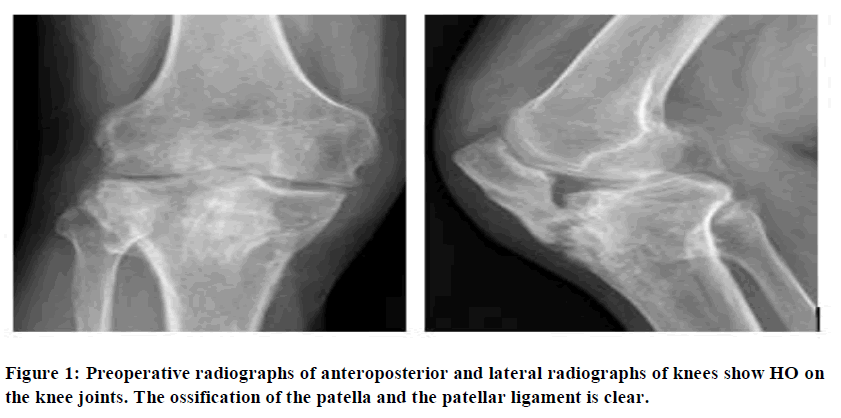

Systemic blood sampling was performed during the patient’s hospitalization. Anteroposteroidal radiographs of the right knee showed hyperosteogeny on the articular surface and the edge of the right knee and slight sharpening of the intercondylar carina. The right knee showed high bone density, the lower edge of the right patella was fused with the proximal tibia, and the space of the right knee had narrowed (Figure 1). Right knee CT examination results show that the right knee had bone hypertrophy, hyperplasia, and broad ligament calcification; most significantly that of the patellar ligament, between the patella and tibial tubercle. There was a small amount of effusion (Figure 2).